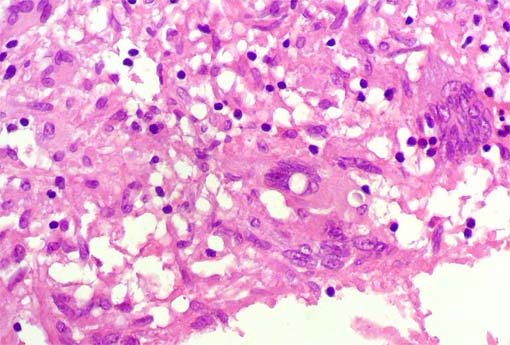

Figura 5.

H&E, X400.